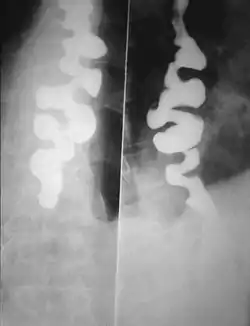

التشنج المريئي المنتشر[1] (بالإنجليزية: Diffuse esophageal spasm) ويُدعى اختصاراً DES، هي إحدى الحالات التي تتميز بانقباضات غير منتظمة منتشرة في أغلب المريء والتي قد تسبب صعوبة في البلع وارتجاع. وفي بعض الحالات قد يسبب بعض الأعراض كآلام الصدر المماثلة لتلك التي تحدثها أمراض القلب. لا تزال أسباب المرض غير معروفة حتى الآن؛ بعض التشوهات الشائعة التي تظهر في التصوير عن طريق أشعة إكس شائعة في تشنجات المريء حيث يأخذ المريء شكل نتوءات سن المفتاح أو حبات المسبحة. ومع ذلك فإن هذه التشوهات لا تنفرد بها تشنجات المريء حيث تتشارك بعض الأمراض الأخرى معها في نفس التشوهات. ولذلك هناك اختبار خاص يجرى لتقييم الوظائف الحركية للمريء يسمي "اختبار الوظائف الحركية للمريء" و الذي يمكنه المساعدة في تحديد الانقباضات العضلية الغير طبيعية في المريء والتي بدورها توحي بوجود تشنجات المريء

- باستخدام الأشعة التشخيصية فإن هناك بعض التشوهات التي تظهر في التصوير عن طريق أشعة إكس شائعة في تشنجات المريء حيث يأخذ المريء شكل نتوءات سن المفتاح أو حبات المسبحة. ومع ذلك فإن هذه التشوهات لا تنفرد بها تشنجات المريء حيث تتشارك بعض الأمراض الأخرى معها في نفس التشوهات .